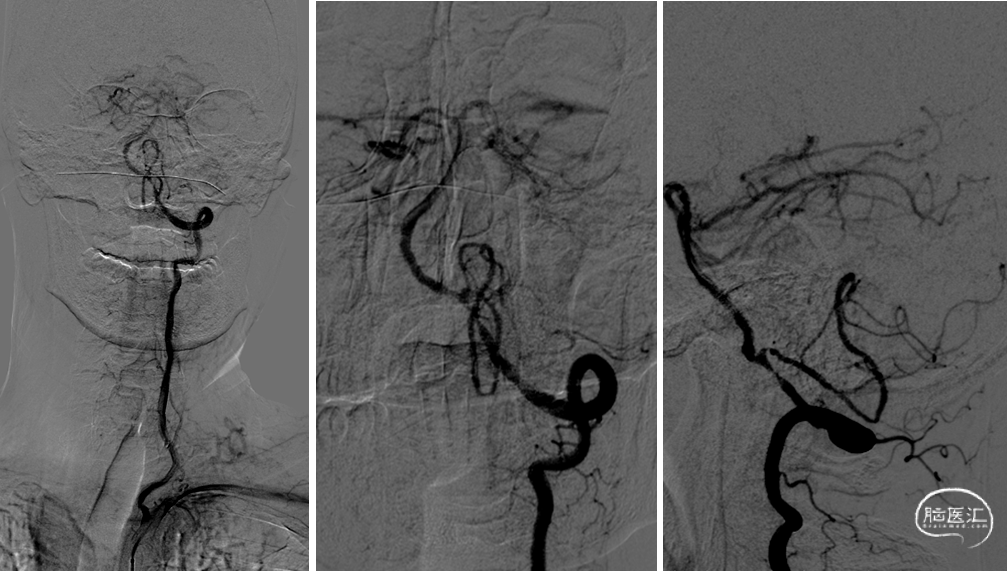

DSA提示:双侧颈内动脉及颅内血管未见明显狭窄,右侧椎动脉优势,左侧椎动脉纤细,V4段闭塞。右侧椎动脉起始处重度狭窄,右椎V4段及基底动脉近端局限性重度狭窄。患者反复间断发作头晕,考虑后循环缺血引起的TIA发作,且强化药物治疗效果不佳,有介入治疗适应症。

左右滑动查看更多

手术过程

全麻后,股动脉置入6F血管鞘,6F导引导管配合超滑导丝至右侧锁骨下动脉建立通路,Synchro-14(200cm)微导丝配合4mm×30mm快交球囊定位V1狭窄扩张。

6F导引导管进入V2后,Synchro-14 (200cm)微导丝配合Gateway 2.5mm×9mm球囊先后进行基底动脉、椎动脉V4段狭窄扩张。

撤出球囊后,Synchro-14(200cm)微导丝配合XT-27至基底动脉远端,从远至近分别置入Neuroform EZ 3mm×15mm及Neuroform EZ 3.5mm×20mm支架。

最后保留微导丝在椎动脉内,将导引导管退至锁骨下动脉后,送入5mm×19mm球扩式支架并释放。